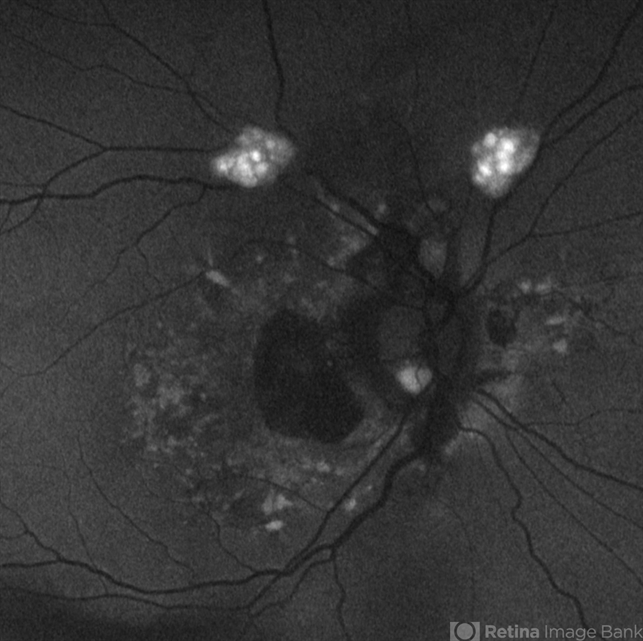

- astrocytic hamartoma, fundus autofluorescence (FAF)

Optos California - Description

- Fundus autofluorescence photo of 55-year-old female with astrocytic hamartoma in association with tuberous sclerosis. No treatment options available, benign. Other findings include; Posterior Vitreous Detachment, Vitreous Hemorrhage, Hereditary Retinal Dystrophy, Vitreous Opacities, Hypertensive Retinopathy.